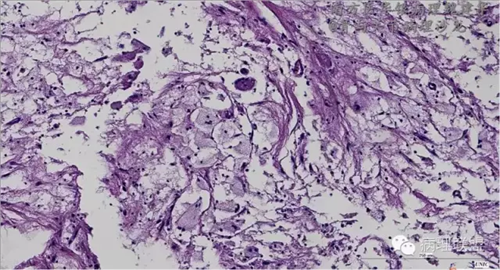

来源于组织细胞的相似性骨病ECD vs RDD 看图说话